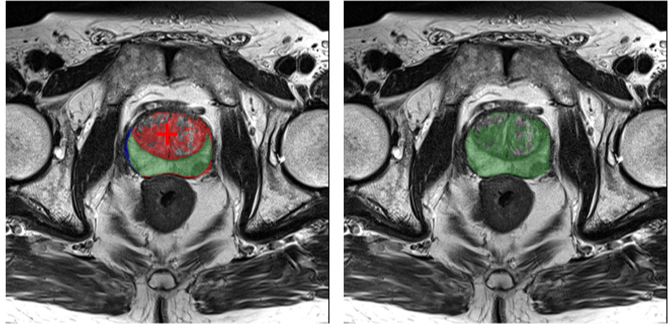

Refer to caption

Figure 1: IBISAgent flexibly supports a wide range of fine-grained biomedical image understanding tasks, including referring and reasoning segmentation. It also handles a novel mask-refinement task that assists annotators in completing partially labeled masks.